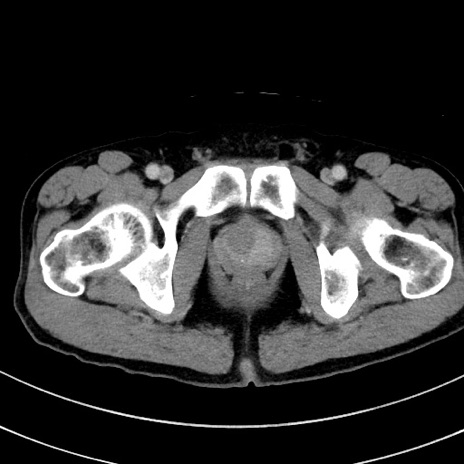

症例8(横断像)

【症例】 60歳代男性

【主訴】 黒色吐物

【現病歴】 4日前から嘔気自覚、2日前の朝食後にも嘔気あり、自分で手で嘔吐反射起こし嘔吐したところ血が混ざっていたため受診。

【既往歴】 5年前汎発性腹膜炎を伴う急性虫垂炎で手術、高血圧、前立腺肥大症、高脂血症

【身体所見】 腹部正中に手術癩痕あり 腹部平坦・軟圧痛なし膨満感あり

【データ】WBC 8400、CRP 4.54